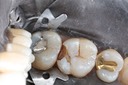

Scott Kanamori #31 finish

Scott Kanamori #31 finish buccal